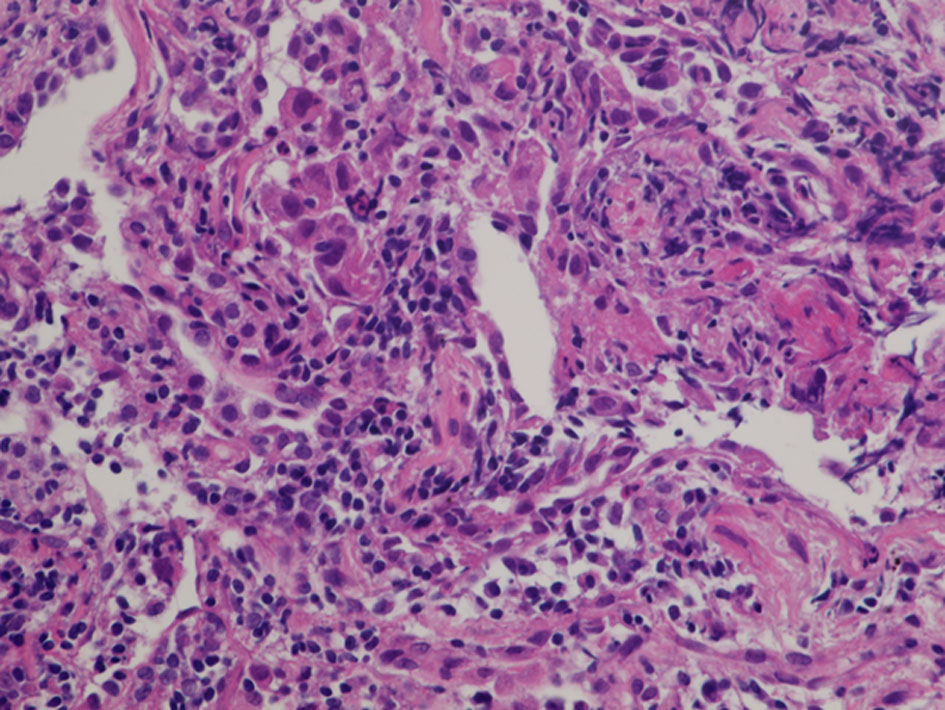

A 60-year-old woman was referred to our department because of a tumor shadow in the left middle lung field in November 2008. She had stopped smoking 5 years before, and was an ex-smoker with 30 pack-year smoking history. She had no significant medical history except for hyperlipidemia. Whole body computed tomography (CT) revealed a 29 × 27 mm sized tumor in the left S4 without distant metastasis. She was diagnosed as lung adenocarcinoma by bronchoscopy from left B4 (Fig. 4). She underwent left upper lobe resection and mediastinal lymph node dissection in December 2008. The pathological staging was p-stage IA (p-T1bN0M0). On genetic examination, no EGFR mutation was detected by PCR clamp method from the surgical specimen. In November 2010, 22 months after the surgery, she visited to our emergency room and presented paralyzed left hand. Brain CT with contrast enhancement revealed a 16 × 13 mm sized tumor with surrounding edema in the right frontal lobe (Fig. 5a). No other distant metastasis was found at that time. We suspected a solitary brain metastasis from lung cancer. She underwent gamma knife radiosurgery (GKR) at another hospital. In August 2011, 10 months after the first GKR, she again received the second GKR for the recurrence at the same brain metastatic site. Thereafter, despite of two courses of carboplatin (area under the curve (AUC) 6 mg/mL/min, day 1) and weekly paclitaxel (60 mg/m2, days 1, 8 and 15), the brain metastasis regrew (Fig. 5b). We started tri-weekly combination chemotherapy of pemetrexed (500 mg/m2, day 1) and intermittent erlotinib (150 mg, days 2 - 16) in November 2011 [9, 10], which reduced the brain metastasis (Fig. 5c). Pemetrexed was discontinued due to grade 3 of edema on the extremities in June 2013, after 28 courses. She continued 150 mg/day of erlotinib, and experienced neither progression nor severe adverse events in October 2022, 11 years after erlotinib initiation. After the initiation of pemetrexed and erlotinib, the Vysis Break Apart ALK fluorescence in situ hybridization (FISH) assay (by LSI Medience Corporation, Tokyo), approved by Japanese medical insurance in April 2012, detected ALK rearrangement in the surgical specimen.

![]() Click for large image | Figure 4. Histology of bronchoscopical specimen of case 1 (H&E stain). H&E: hematoxylin and eosin. |